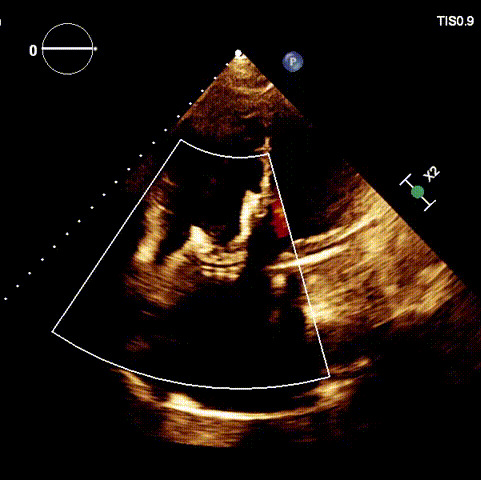

術前超聲心動圖及經食道超聲提示

1.二尖瓣位機械瓣位置及功能未見異常;2.雙房及右室明顯擴大(左房收縮容積115ml,右房收縮容積370ml,右室中段左右徑65mm,右室FAC37%),下腔靜脈及冠狀靜脈竇擴張(下腔靜脈直徑44mm,冠狀靜脈竇直徑22mm);3.極重度三尖瓣反流(FTR 6+)。

術前超聲

術后超聲